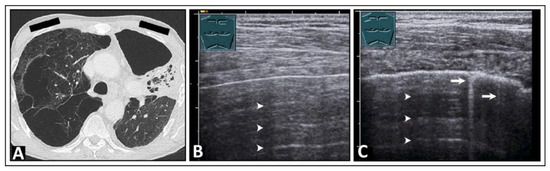

5. Pneumonia

6. Interstitial Lung Disease